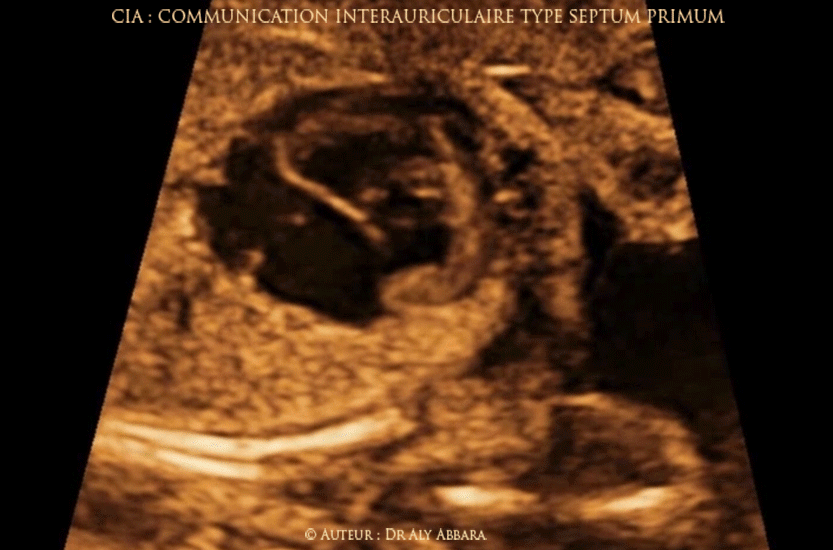

Vidéo et image animée échocardiographiques montrant une malformation cardiaque congénitale isolée ; il s'agit d'une communication inter-auriculaire (CIA) type septum primum ou atrial septal defect (ASD I).

Cette CIA se caractérise par l'absence complète du septum primum entraînant la constitution d'une communication interauriculaire adjacente les valves auriculo-ventriculaires (mitrale et tricuspide) et associée d'un alignement de ces valves. Cette CIA est une des formes des canaux atrioventriculaires (CAV).

Le septum primum est la composante basse du septum interauriculaire, il est au contact avec le tissu séparant les deux valves auriculo-ventriculaires.

Fœtus âgé de 28 SA.